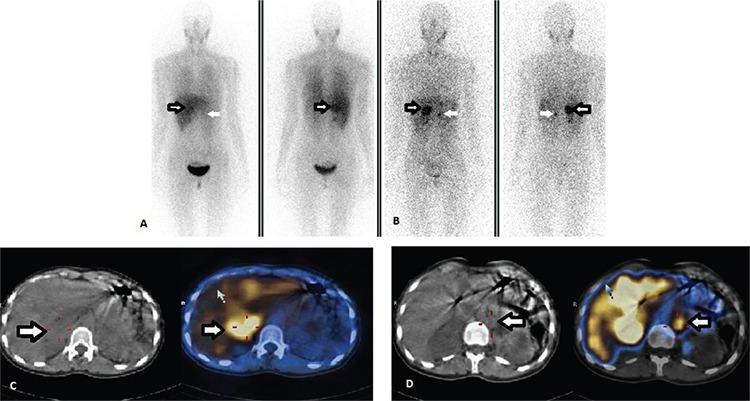

Von Hippel-Lindau syndrome (VHLS) is an autosomal dominant hereditary familial disorder characterized by development of malignant and benign neoplasms. Differential diagnosis of the adrenal and pancreatic masses are difficult in patients with VHLS. Iodine-123 metaiodobenzylguanidine (I-123 MIBG) and indium-111 somatostatin receptor scintigraphies (In-111 SRS) have important roles in the differential diagnosis of adrenal and pancreatic masses in those patients. In this case report, we present the findings of I-123 MIBG single-photon emission computerized tomography (SPECT/CT) and In-111 SRS SPECT/CT in three members of a family with VHLS. In case 1, a residual neuroendocrine tumor (NET) was detected in the head of pancreas on In-111 SRS SPECT/CT images. In case 2 and 3, I-123 MIBG SPECT/CT confirmed the adrenal masses as pheochromocytoma, and the extra-adrenal mass as NET, before surgery. We thought that In-111 SRS and I-123 MIBG scan might be helpful in the routine work up of VHLS patients for diagnostic and therapeutic purposes. Hybrid SPECT/CT system may improve diagnostic accuracy of planar images since it assesses morphologic and functional information together.

冯·希佩尔-林道综合征(VHLS)是一种常染色体显性遗传性家族性疾病,其特征为恶性和良性肿瘤的发生。对于VHLS患者,肾上腺和胰腺肿块的鉴别诊断较为困难。碘-123间碘苄胍(I-123 MIBG)和铟-111生长抑素受体闪烁扫描(In-111 SRS)在这些患者肾上腺和胰腺肿块的鉴别诊断中发挥着重要作用。在本病例报告中,我们展示了I-123 MIBG单光子发射计算机断层扫描(SPECT/CT)和In-111 SRS SPECT/CT在一个VHLS家族三名成员中的检查结果。病例1中,In-111 SRS SPECT/CT图像在胰头检测到残留神经内分泌肿瘤(NET)。病例2和3中,I-123 MIBG SPECT/CT在手术前确诊肾上腺肿块为嗜铬细胞瘤,肾上腺外肿块为NET。我们认为In-111 SRS和I-123 MIBG扫描可能有助于VHLS患者进行常规检查以用于诊断和治疗目的。混合SPECT/CT系统可同时评估形态学和功能信息,从而提高平面图像的诊断准确性。